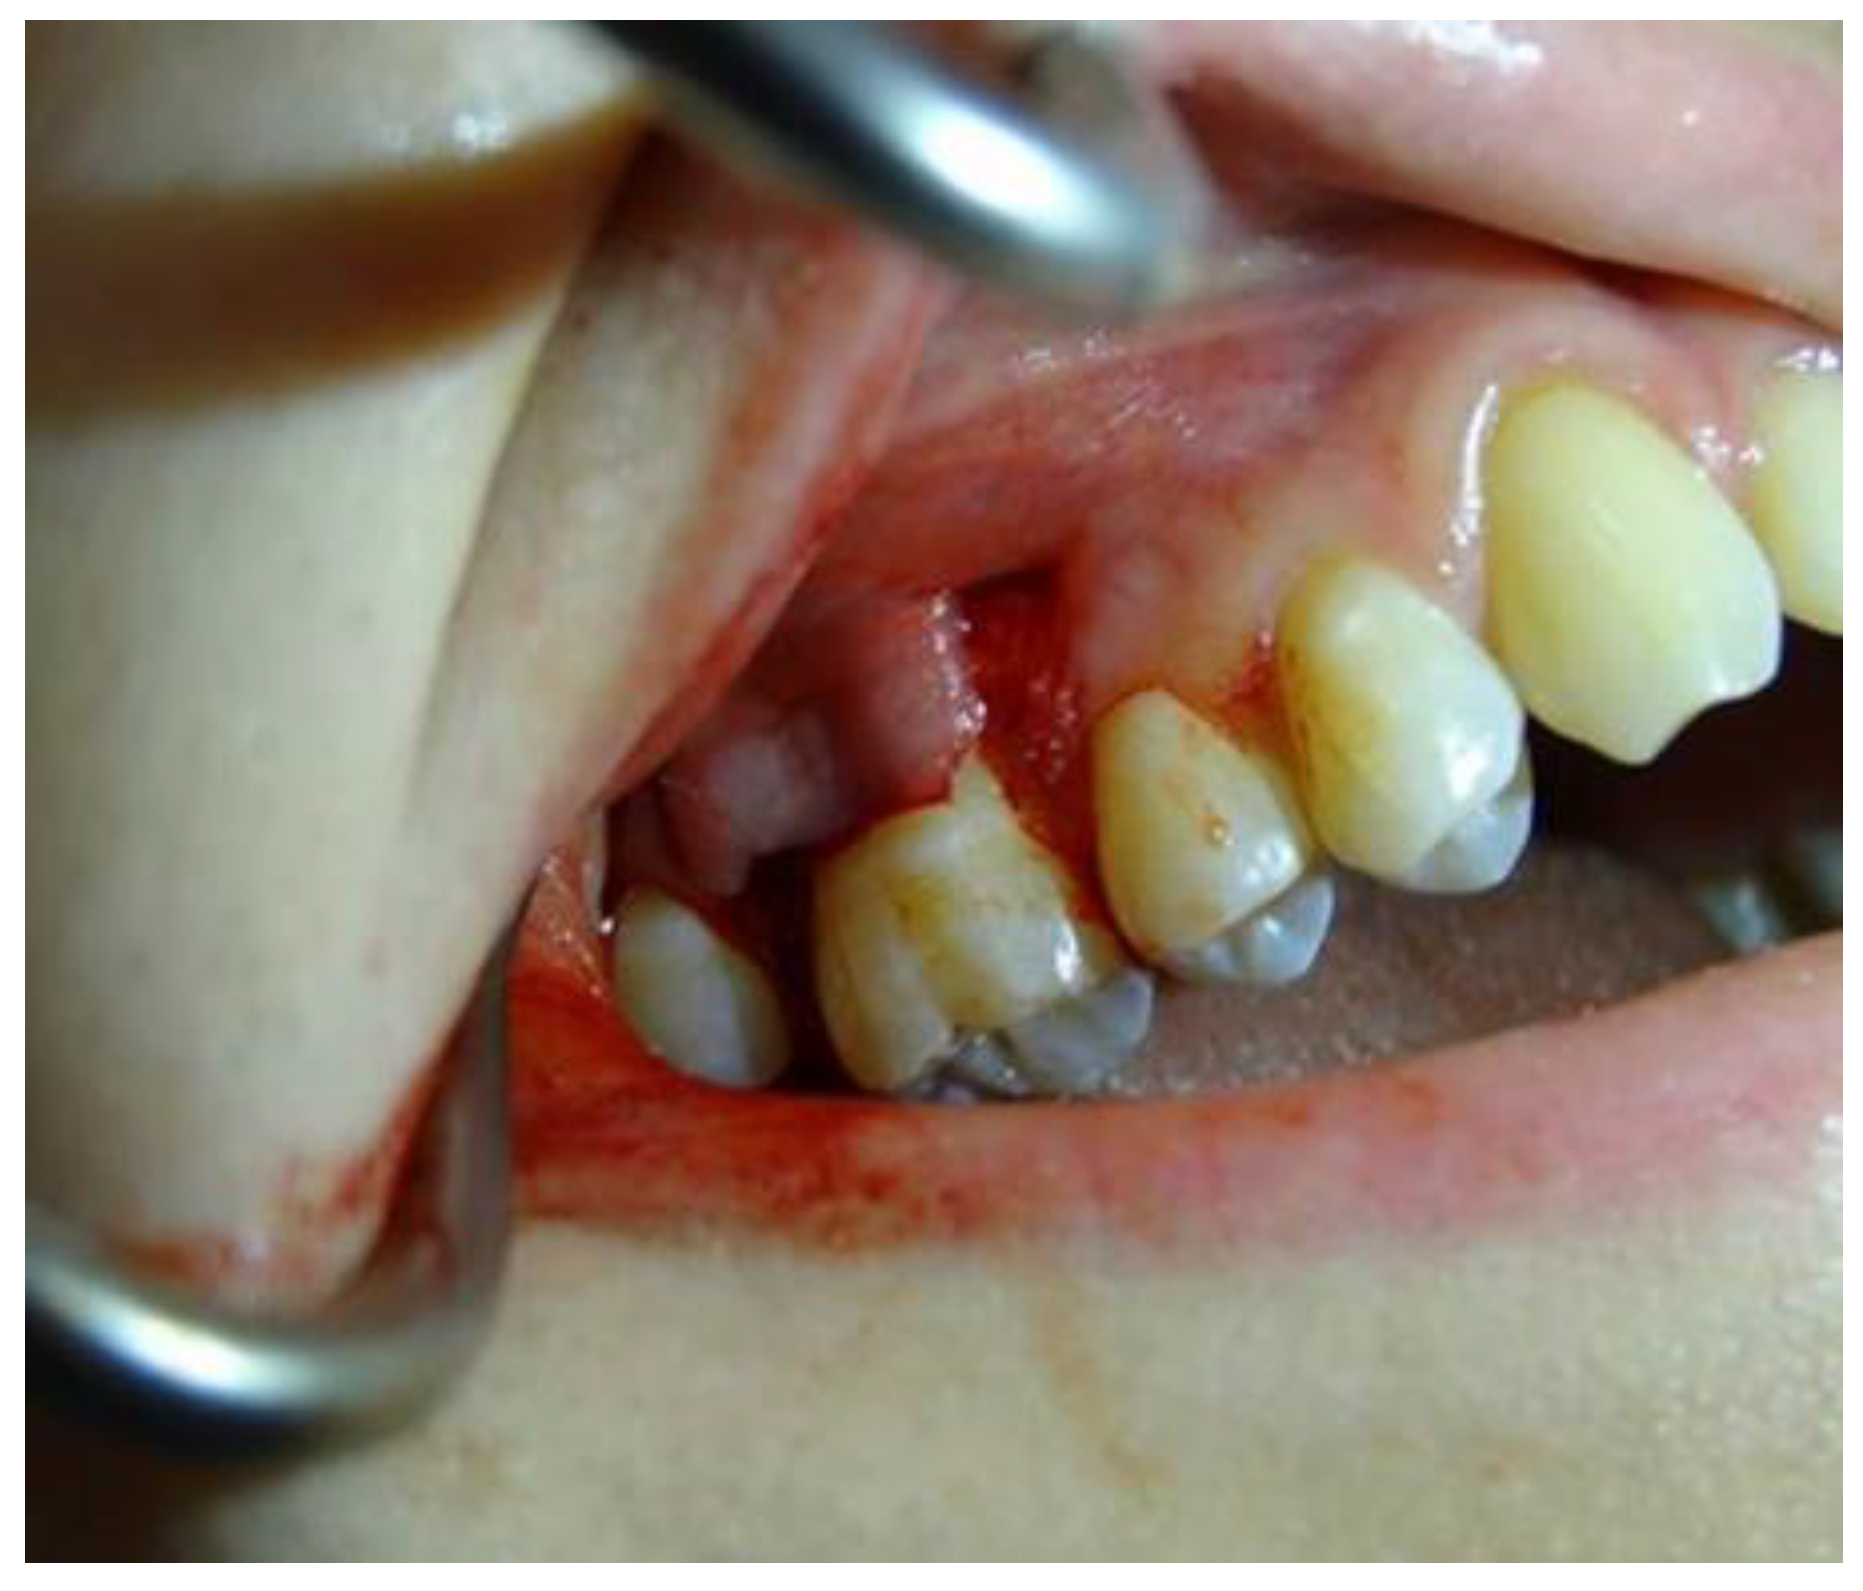

2.1.4. Surgical Procedures